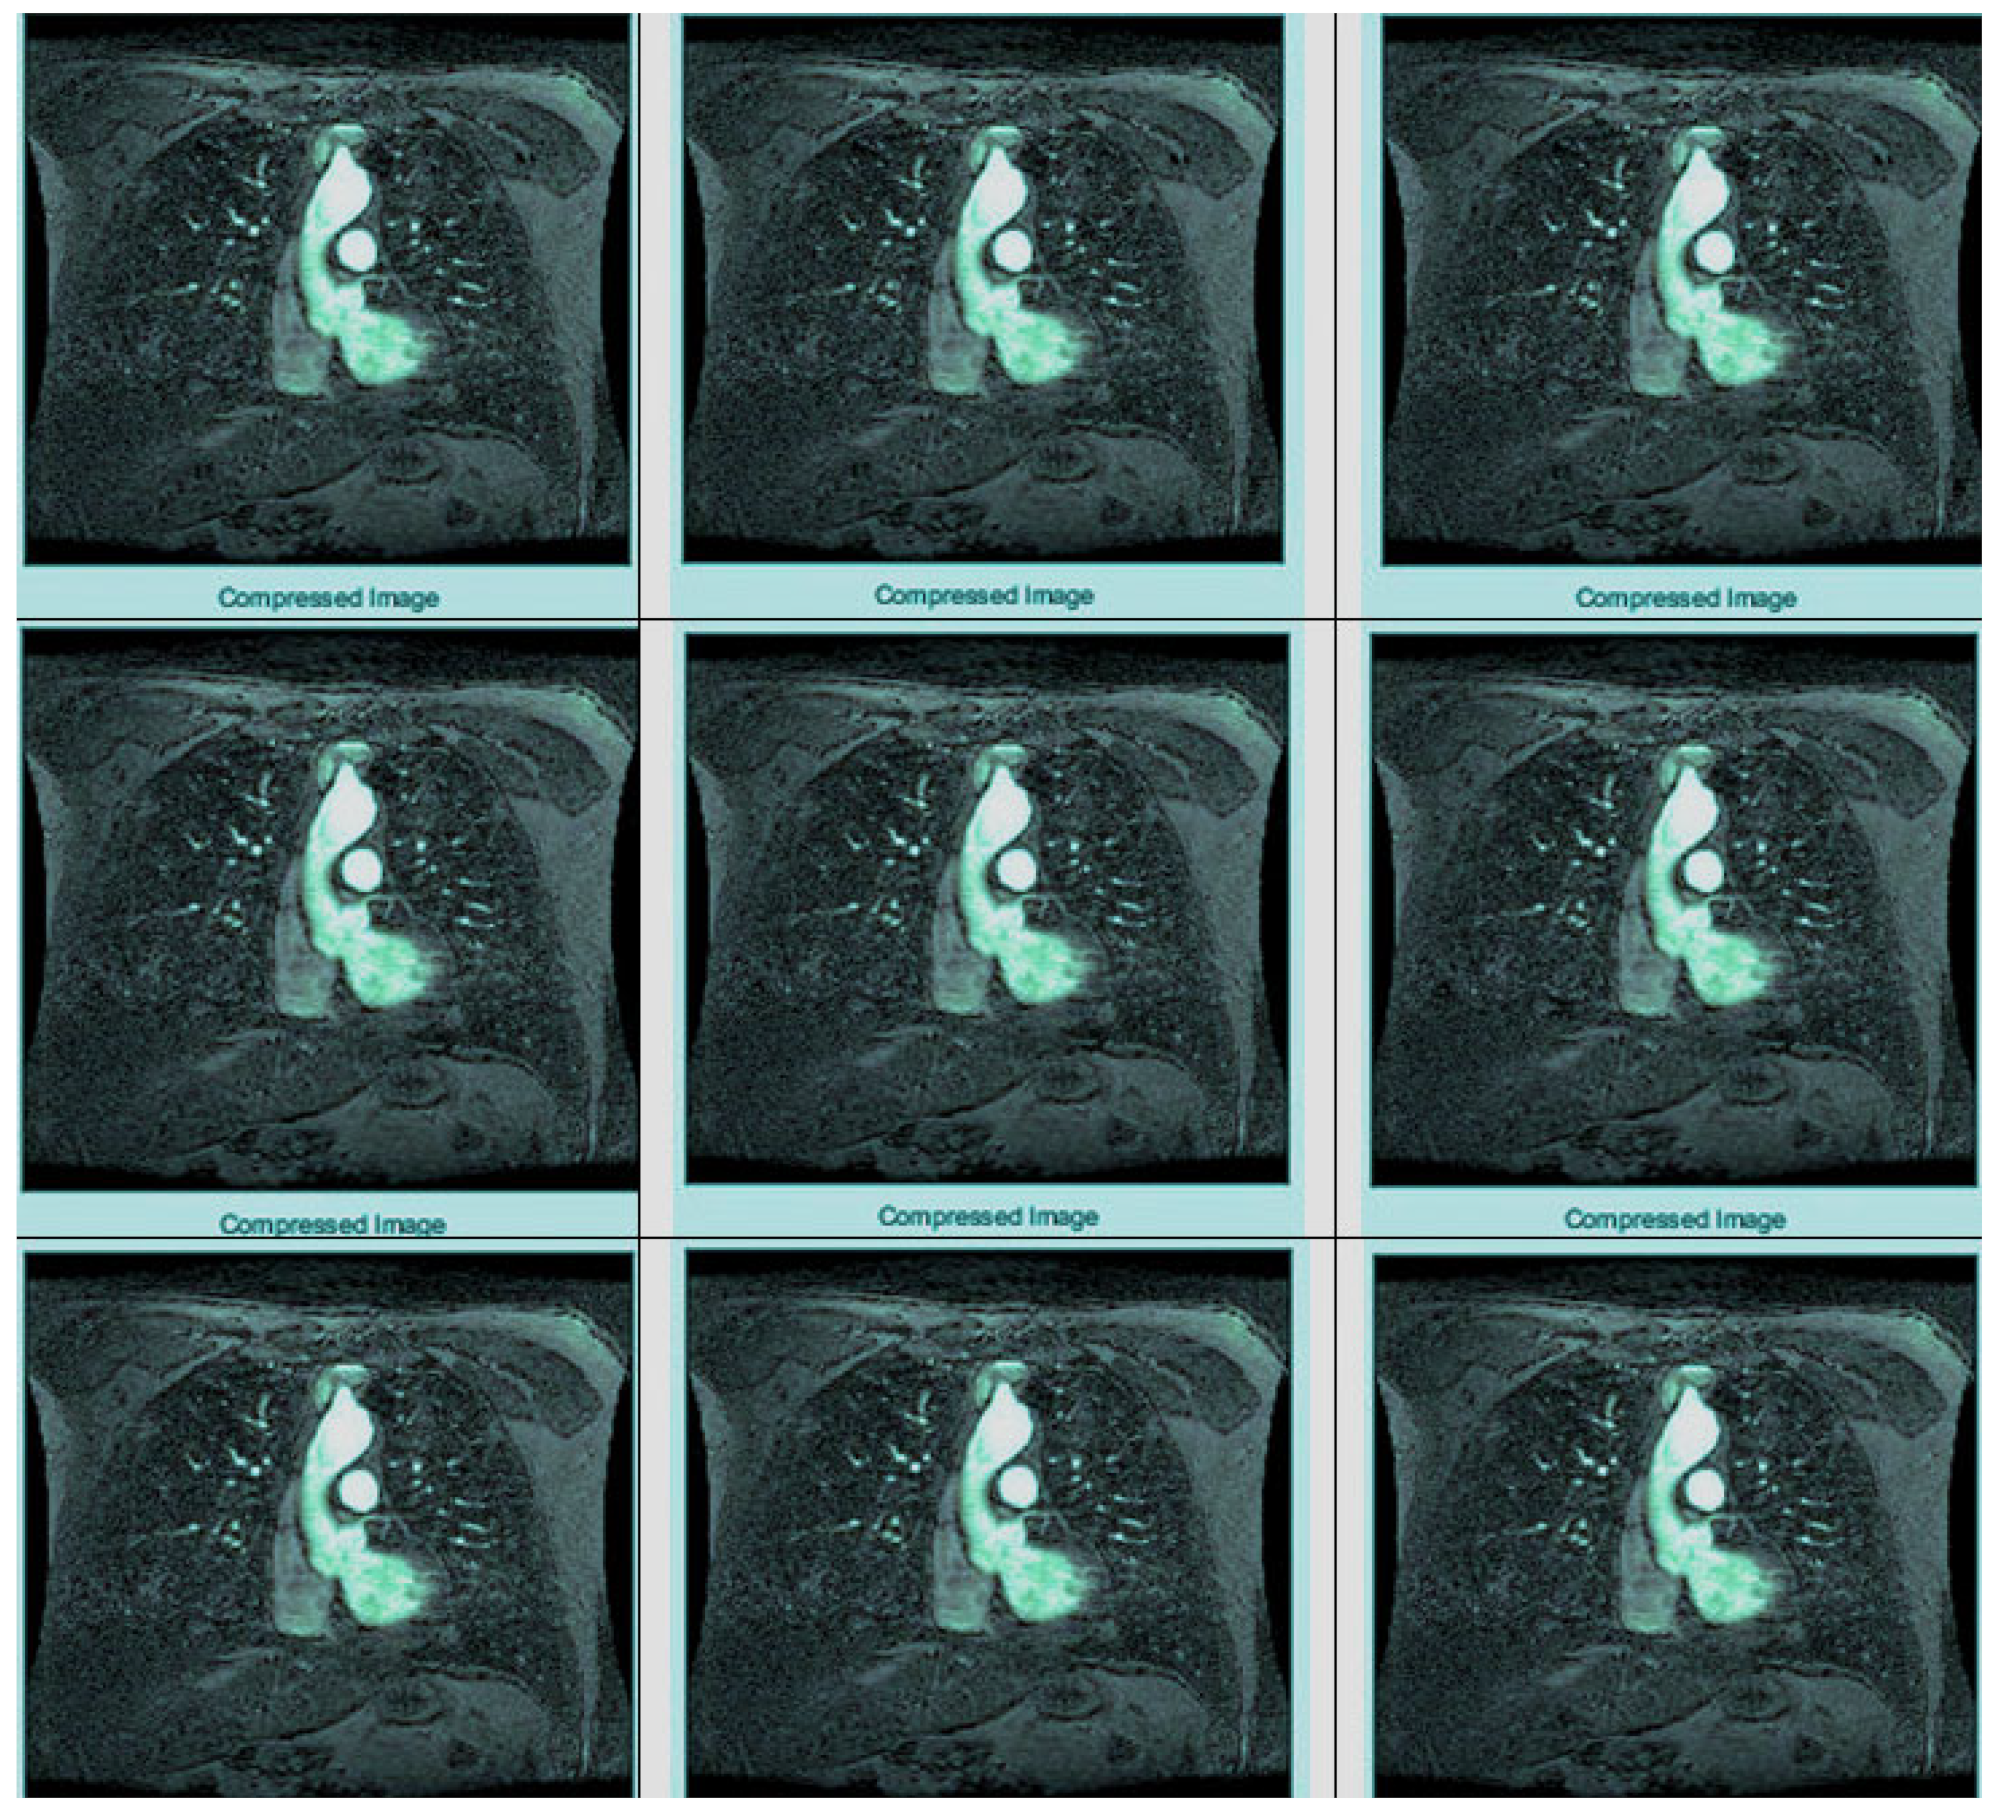

The “dwt2” method is used for the conversion. In the DWT process, the original image is decomposed into up to two levels using the “Haar” wavelet. This decomposition produces horizontal, vertical, diagonal, and proximity components. The decomposed components are reconstructed using the DIWT to recover the original image. This strategy is illustrated in Figure 2, and the compression method takes a decomposed image as input and compresses it using a wavelet packet compression technique using “Haar” wavelet packets. The compression method, “wpdencmp,” uses a soft thresholding technique that uses wavelet packets to compress the image and compute the threshold. This compression concept is illustrated in Figure 3, along with histograms of the original and compressed images. A step-by-step compaction process is shown in Figure 4. At each level, the images are refined, and the differences between levels are visible. The higher the number of coding levels of compression, the higher the image’s compression ratio and recovered energy. The compressed image is decompressed by wavelet packet reconstruction using the accounting matrix values of the decomposed image. Horizontal, vertical, diagonal, and proximity components are extracted from the decompressed image, and an IDWT is applied to recover the original image. A title image embedded in the patient data is visualized.

Figure 4.

Applying DWT.

In Figure 3, the steganography image of the brain hemorrhage is taken, and DWT is applied. After compression, the compressed image is displayed as a bar graph. The wavelet reconstruction method recovers the compressed image from the compressed image. The target image is retrieved from the decompressed image by applying the IDWT method to the previous step. Figure 4 represents the DWT and IDWT of the brain hemorrhage image. A sample segmentation of the transformed image is also displayed.

Figure 5 represents the histograms of the steganography and decomposed and compressed images in red, blue, and pink colors, respectively. The obtained outcome shows that the adopted methodology is efficient regarding high-resolution lossless compression of medical images. In the resultant images, the novelty of the work is apparent; it can be seen that the proposed methodology enables excellent elaboration and enhancement using improved WTs and lossless compressions. Figure 6 represents the transition steps of the wavelet packet compression technique, where the images are clearly distinguished from one another.

Figure 6.

Compression of the transformed image.